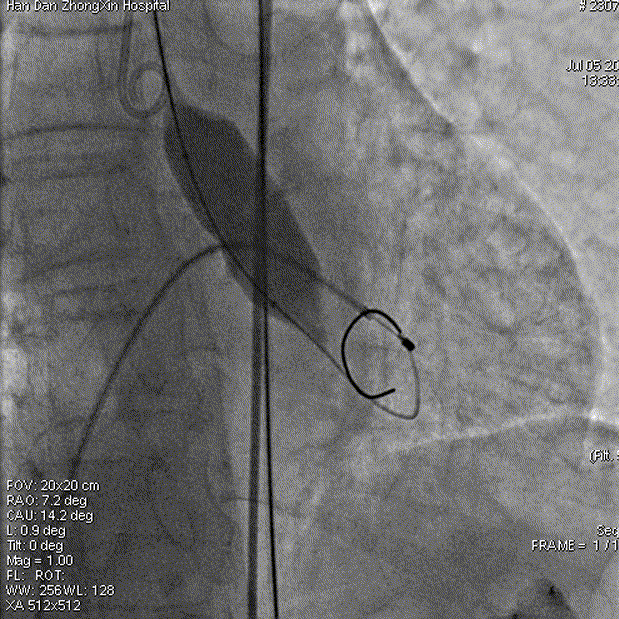

球囊预扩

工作钢丝送入左室进行起搏,180bpm起搏下预扩张主动脉瓣,完全扩张后,主动脉根部造影无返流,回撤球囊停止临时起搏,延大鞘进入输送系统,定位输送系统位置,瓣膜释放1/3时,起搏160bpm,快速释放至3/4处,瓣膜正常工作后,观察冠脉风险。